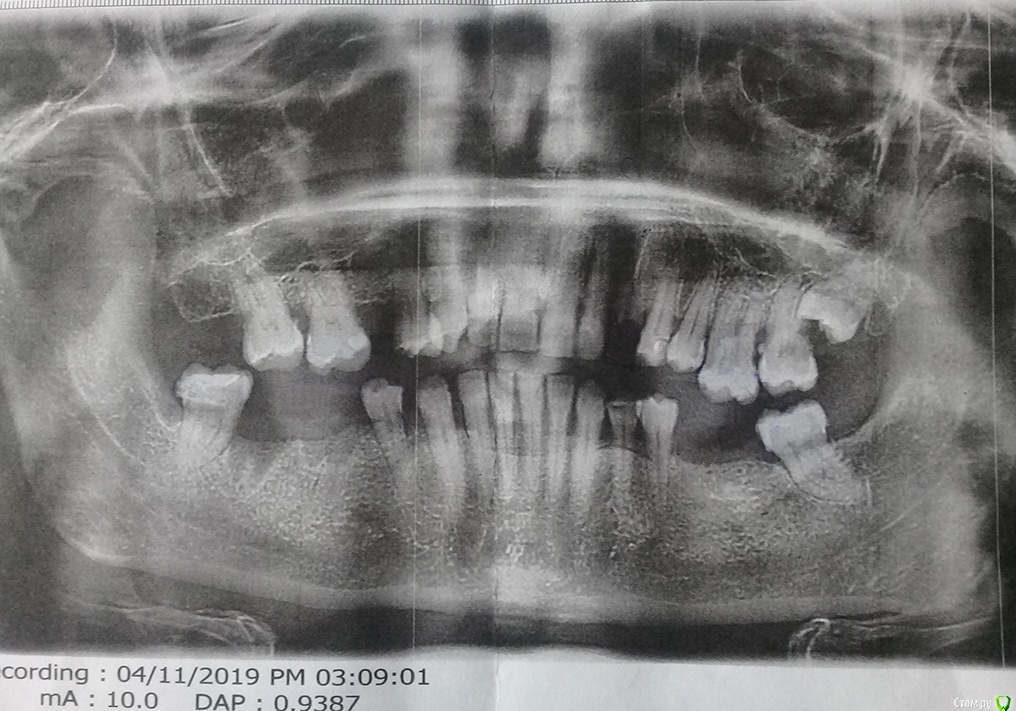

Марина В. Опубликовано 15 мая, 2019 Поделиться Опубликовано 15 мая, 2019 Добрый день! Пожалуйста, посоветуйте, что можно сделать с моими остатками зубов (снимок прилагаю). Была у местного врача (Подмосковье). Предлагает единственный вариант: вкладку с коронкой на верхний клык, остальное – мосты из металлокерамики дуцерам или норитаке. Меня расстраивает то, что для установки этих мостов нужно депульпировать 7 зубов. Если честно, жалко до слез. Если других вариантов нет, может лучше сделать хороший съемный протез на нижнюю челюсть?Решила искать специалиста в Москве. Есть ли смысл? Или тут действительно без вариантов? Заранее благодарна за любые рекомендации. Ссылка на комментарий